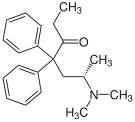

Amidones

Structures

| Amidones | ||||